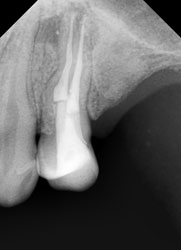

На этом рентгеновском снимке видны, в первую очередь, «пустые» корневые каналы и довольно больших размеров очаг воспаления (то, что часто называют гранулемой, кистой) на верхушке одного из корней. В общем итоге в одном зубе был сконцентрирован целый букет ошибок и недоделок, одним словом, это образец недобросовестной работы стоматолога. Я стараюсь о коллегах всегда говорить или хорошо или молчать, но в данном случае надо смотреть правде в глаза – зуб загублен именно стоматологом. Никаких объективных сложностей для качественной работы изначально здесь не было. Зато появились теперь. Прогноз на будущее для таких зубов всегда строится, исходя из 2 основных проблем – насколько приведет к успеху повторное лечение каналов и насколько будет успешной попытка адекватного восстановления зуба после этого. Оценив вероятность долговременного успеха этих двух составляющих, можно решать, стоит ли «спасать» зуб от щипцов хирурга. Ведь, в любом случае, лечение стоит денег, а гарантировать результат здесь невозможно. Можно только предполагать вероятность успеха. В данном случае каналы не выглядели непроходимыми. Да и восстановить зуб коронкой, даже несмотря на большую степень разрушения, все еще представлялось возможным. А потому было принято решение о начале лечения.